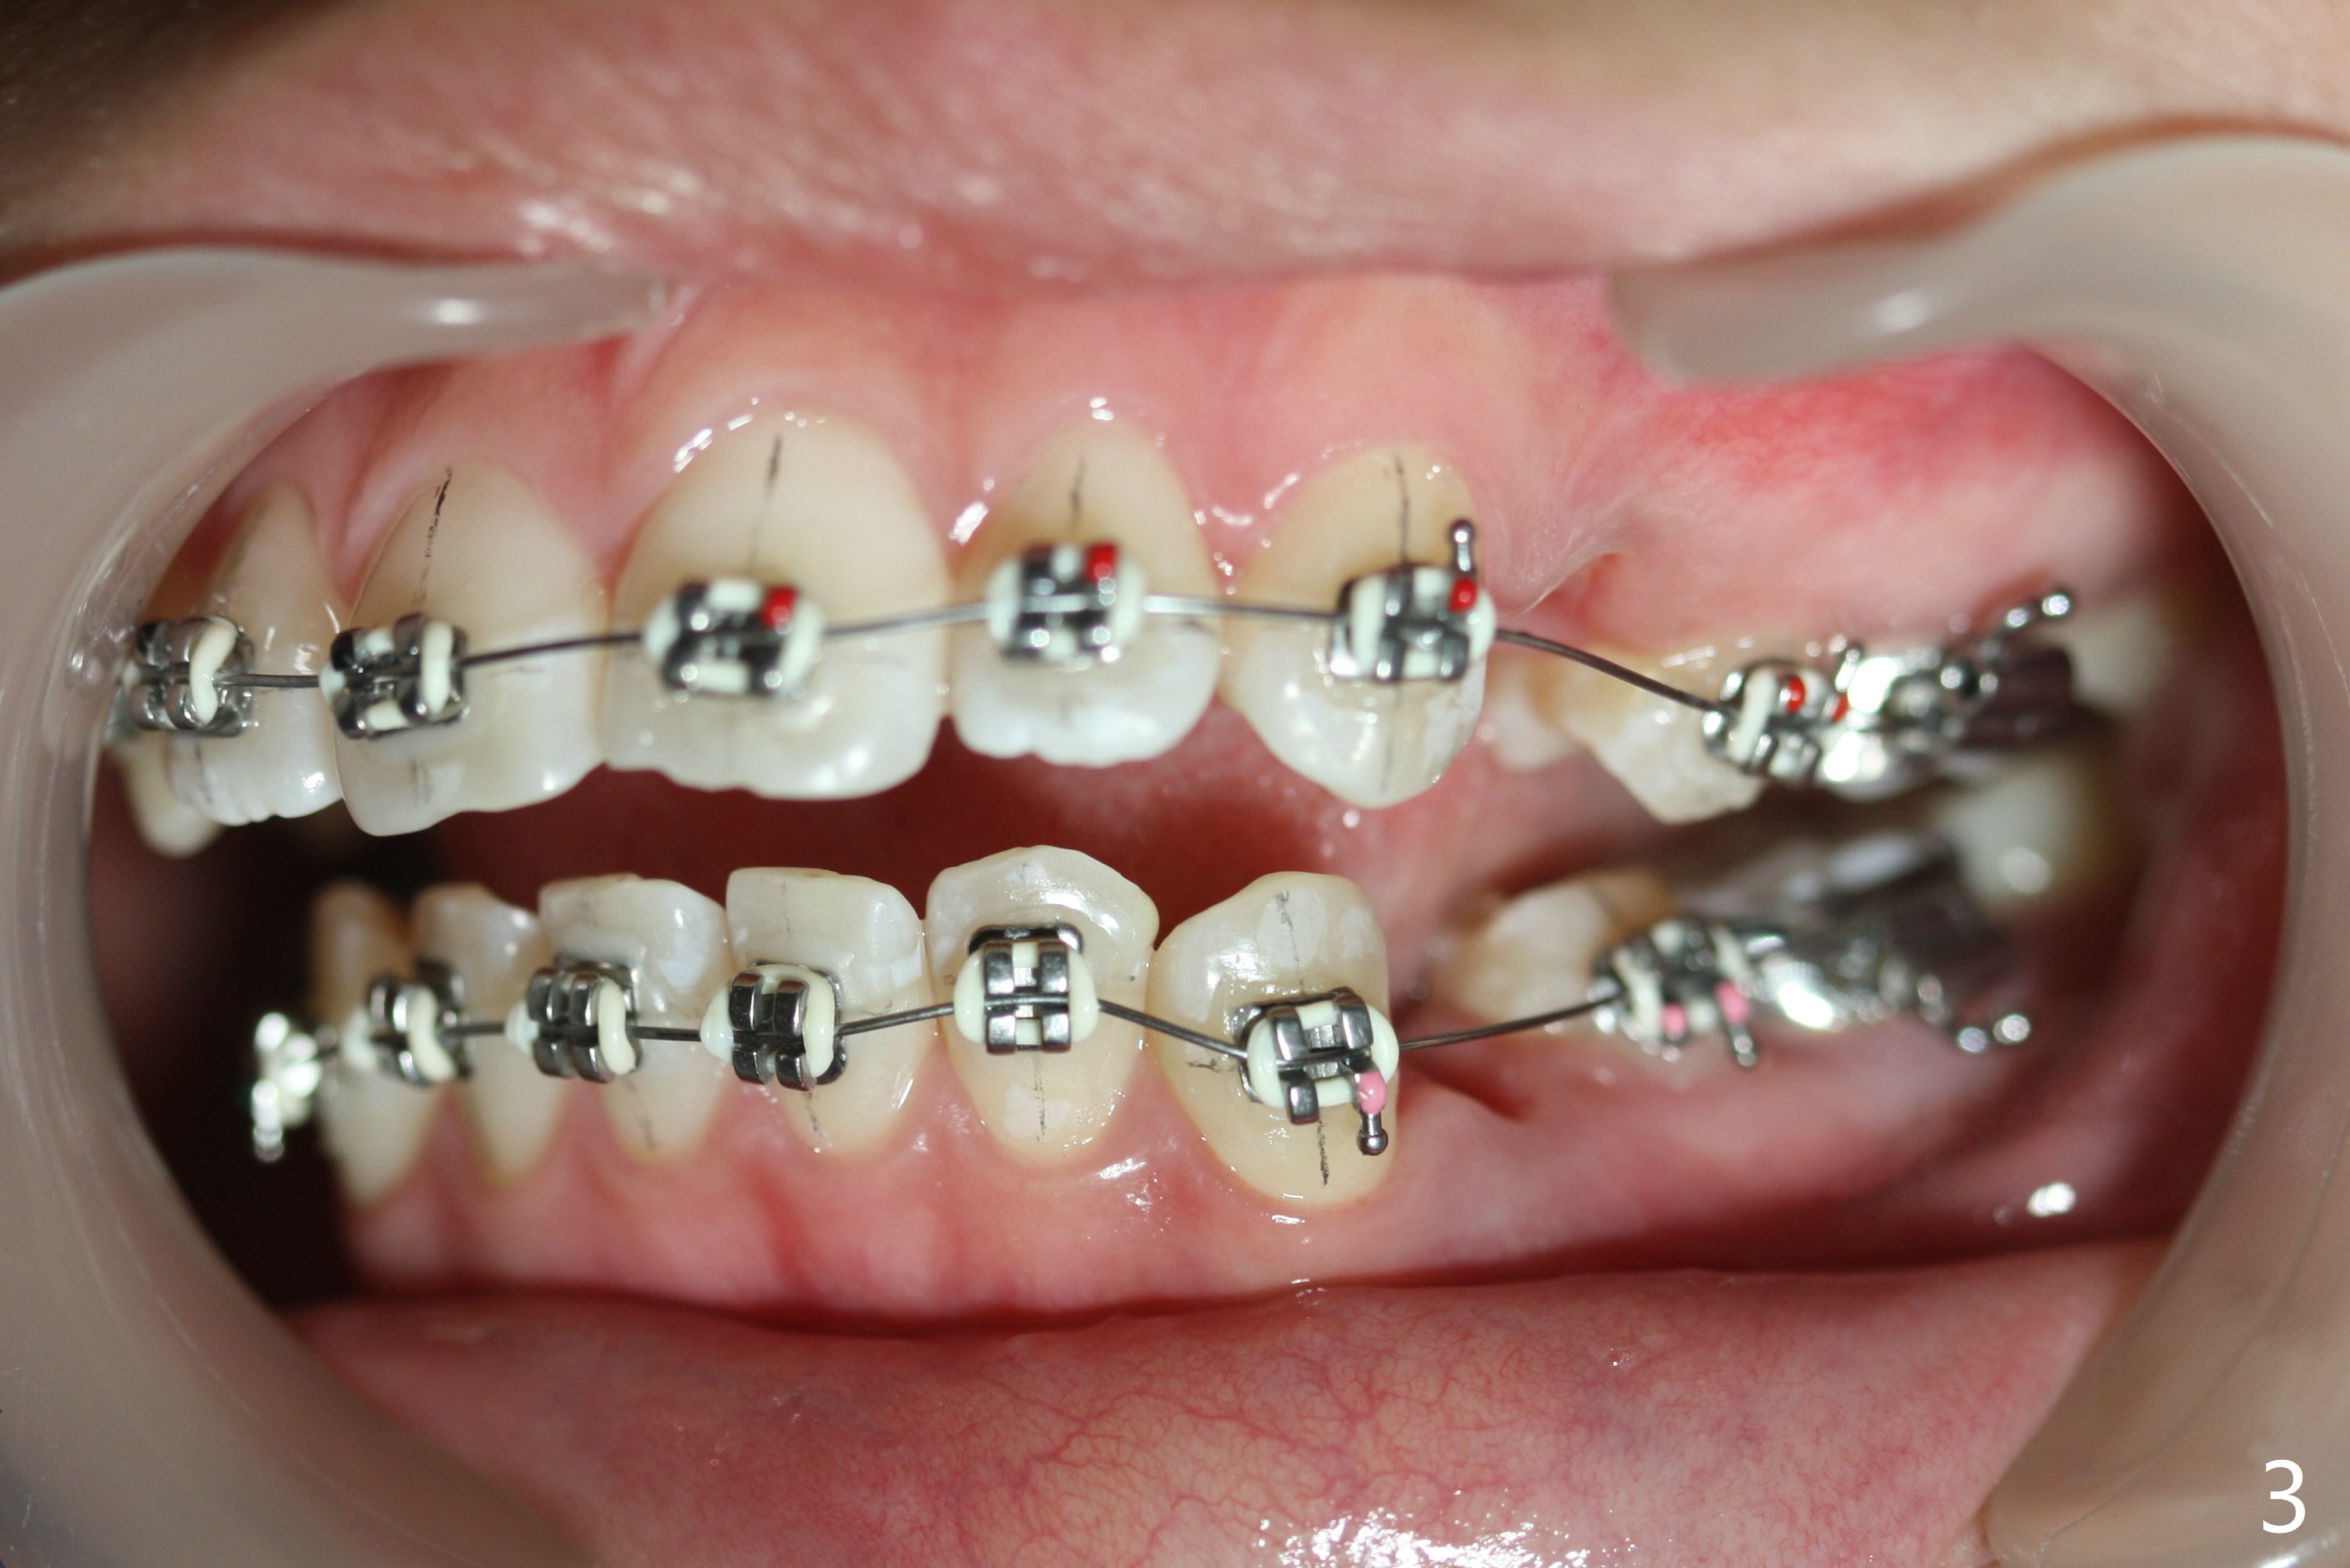

Two weeks post extraction of 4 bicuspids, brackets and bands are placed in 20 teeth (Fig.1-3, 14 niti). No bands are placed at 7s because of short crowns and tight contacts. When 16x16 wires are used, start Class II retraction. The latter is initiated with elastics when 18 ss wires are placed (Fig.4,5). U3s have been distalized with closed springs for 3 months (Fig.6,7). U2s are close to distalization 13 months post banding, 3.5 months post posted wire (Fig,8,9) with overjet (Fig.10). Class II retraction is re-initiated. When the upper incisors are retracted, the anterior overjet remains large. It appears that U6s have been retracted anterior, as indicated by the space between U6/7 (Fig.11), because of no use of U7s as anchors. Brackets are just placed with 18 niti arch wire. They will be retracted distal using the rest of the upper teeth and lower teeth (using Class II retraction) as anchor. There is root resorption of the upper anteriors 2 years 1 month post banding (Fig.12,13).